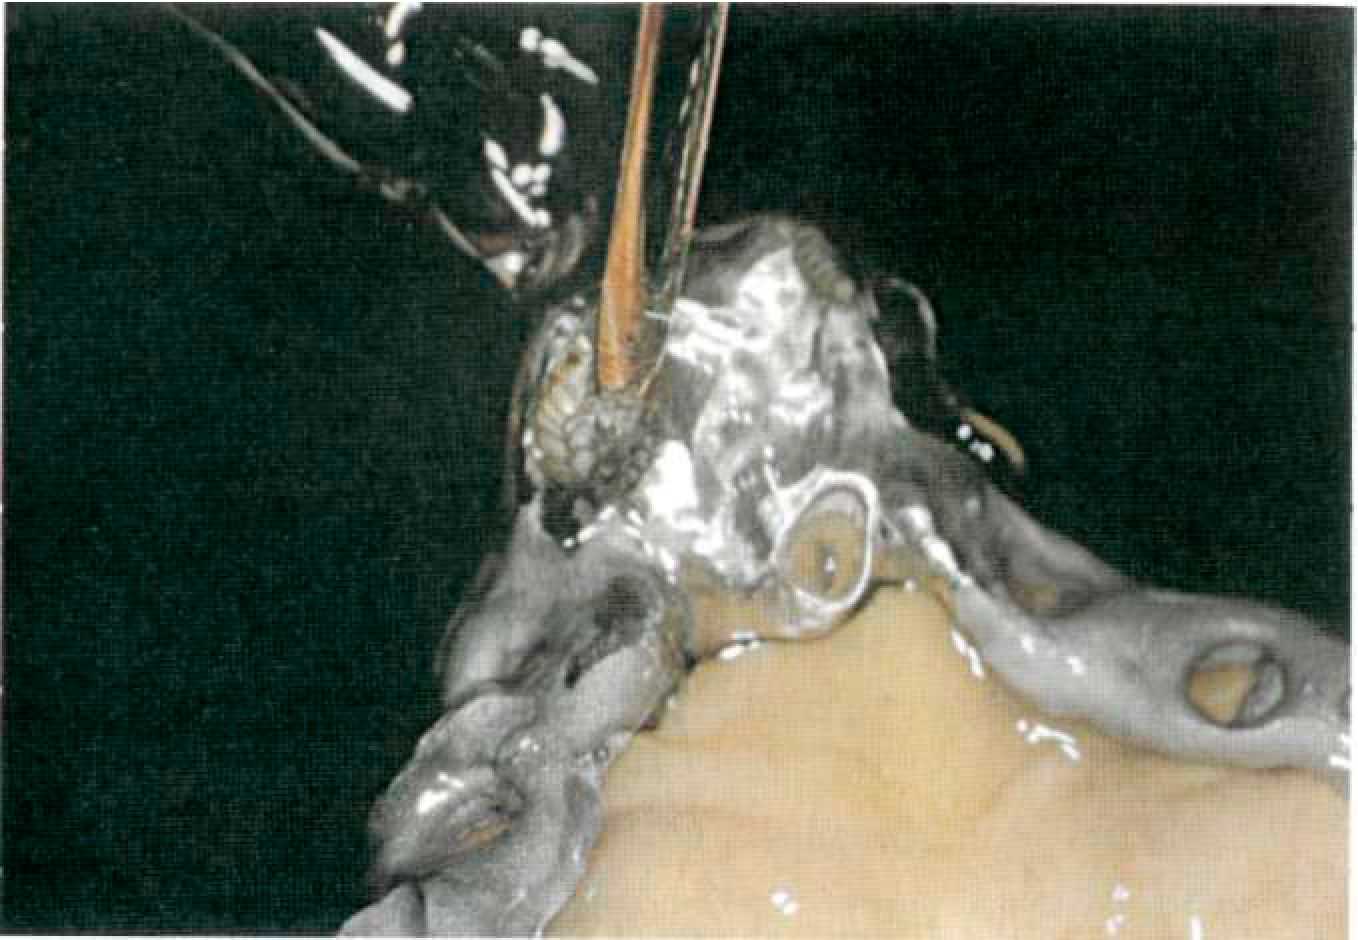

На огнеупорной модели изготавливают восковой каркас съемной части протеза и отливают. Отлитый каркас припасовывают на первичные коронки, ответные вторичные наружные телескопические коронки полируют изнутри мелкодисперсной алмазной пастой и подготавливают всю систему к электроискровой эрозии (рис. 139). Этап 11. Электроискровая эрозия производится на специальном оборудовании фирмы SAE. Рабочую модель с помещенными первичными коронками, закрепленную на рабочем столике, устанавливают в аппарат искровой эрозии (рис. 140). Медный электрод вертикально ориентируют в утолщение, созданное для производства эрозионного паза. Затем на первичных коронках закрепляют каркас съемной части протеза и подают сигнал к началу электроискровой эрозии, которая производится в автоматическом режиме (рис. 141). После проведения электроискровой эрозии зубной техник припасовывает в образовавшиеся пазы фрикционные штифты выбранного диаметра, фиксирует их контактной сваркой к металлическому каркасу съемной части (рис. 142).